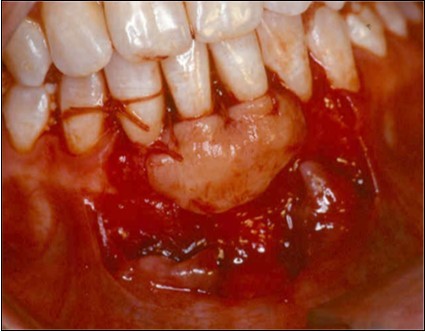

A partial thickness flap is created with two vertical incisions placed at least one-half to one tooth wider mesiodistally than the area of gingival recession. The coronal margin of the flap is started with a horizontal sulcular incision to preserve all existing radicular gingiva. The interproximal papillae are left intact. The flap dissection is partial thickness leaving connective tissue over the existing bone and / or root surfaces. The root of the involved tooth is carefully scaled and planed until its surface is smooth and hard. Er-YAG laser is then applied to its surface to promote root biomodification, at powers ranging from 25 to 50 mJ/pulse/sec. (Figure 3, Figure 3A).

Figure 3A.Er-Yag laser being applied to promote root biomodification